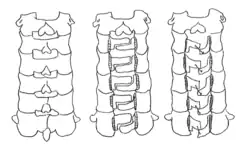

Z-shaped laminoplasty

The C2 to C7 laminae are thinned out with a drill. It is important to decompress more than one region of the laminae. A z-shape is cut on the laminae, and the laminae are lifted and connected with a suture.[1]

Open door laminoplasty

The C2 to C7 laminae are drilled at the lateral borders of the laminae. One side of the bone is completely cut, while the other side acts as a hinge. The laminae are then lifted to increase space in the spinal canal. The flap of the laminae is kept open with a suture that is fixed to the facet capsule.[1][5]

Double door laminoplasty

At the midline of the vertebral laminae, a drill is used to cut the bone. The lateral sides of the laminae serve as a hinge that allows expansion of the spinal canal. Specifically, the inner cortex of the lateral portion was part of the hinge. An artificial spacer is used to keep the opening fixed. One common spacer that is used is hydroxyapatite.[1]